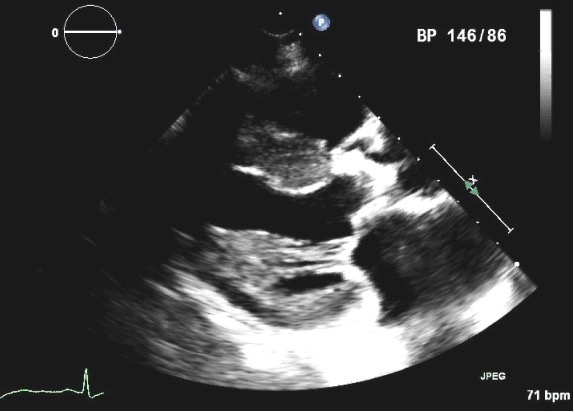

Structural valve deterioration (SVD) occurs almost exclusively in bioprosthetic valves, and is due to a combination of leaflet calcification and disruption of the collagen fibers composing of the valve (Fig. 3). These lead to progressive stiffening resulting in stenosis of the prosthesis, or tearing of the leaflets with the expected regurgitation that ensues. A less common form of SVD is stent creep which occurred more frequently in older generation bioprosthetics. This was characterized by an inward deflection of the stents and resulted in stenosis.

Fig. 3.Parasternal long axis view of a four year old 21 mm St Jude Trifecta pericardial aortic valve in a patient who presented with progressive exertional dyspnea and presyncope and was found to have severe prosthetic obstruction. Note the highly echogenic aortic bioprosthesis, suggesting a heavily calcified valve with stenotic orifice, which was confirmed during valve replacement.